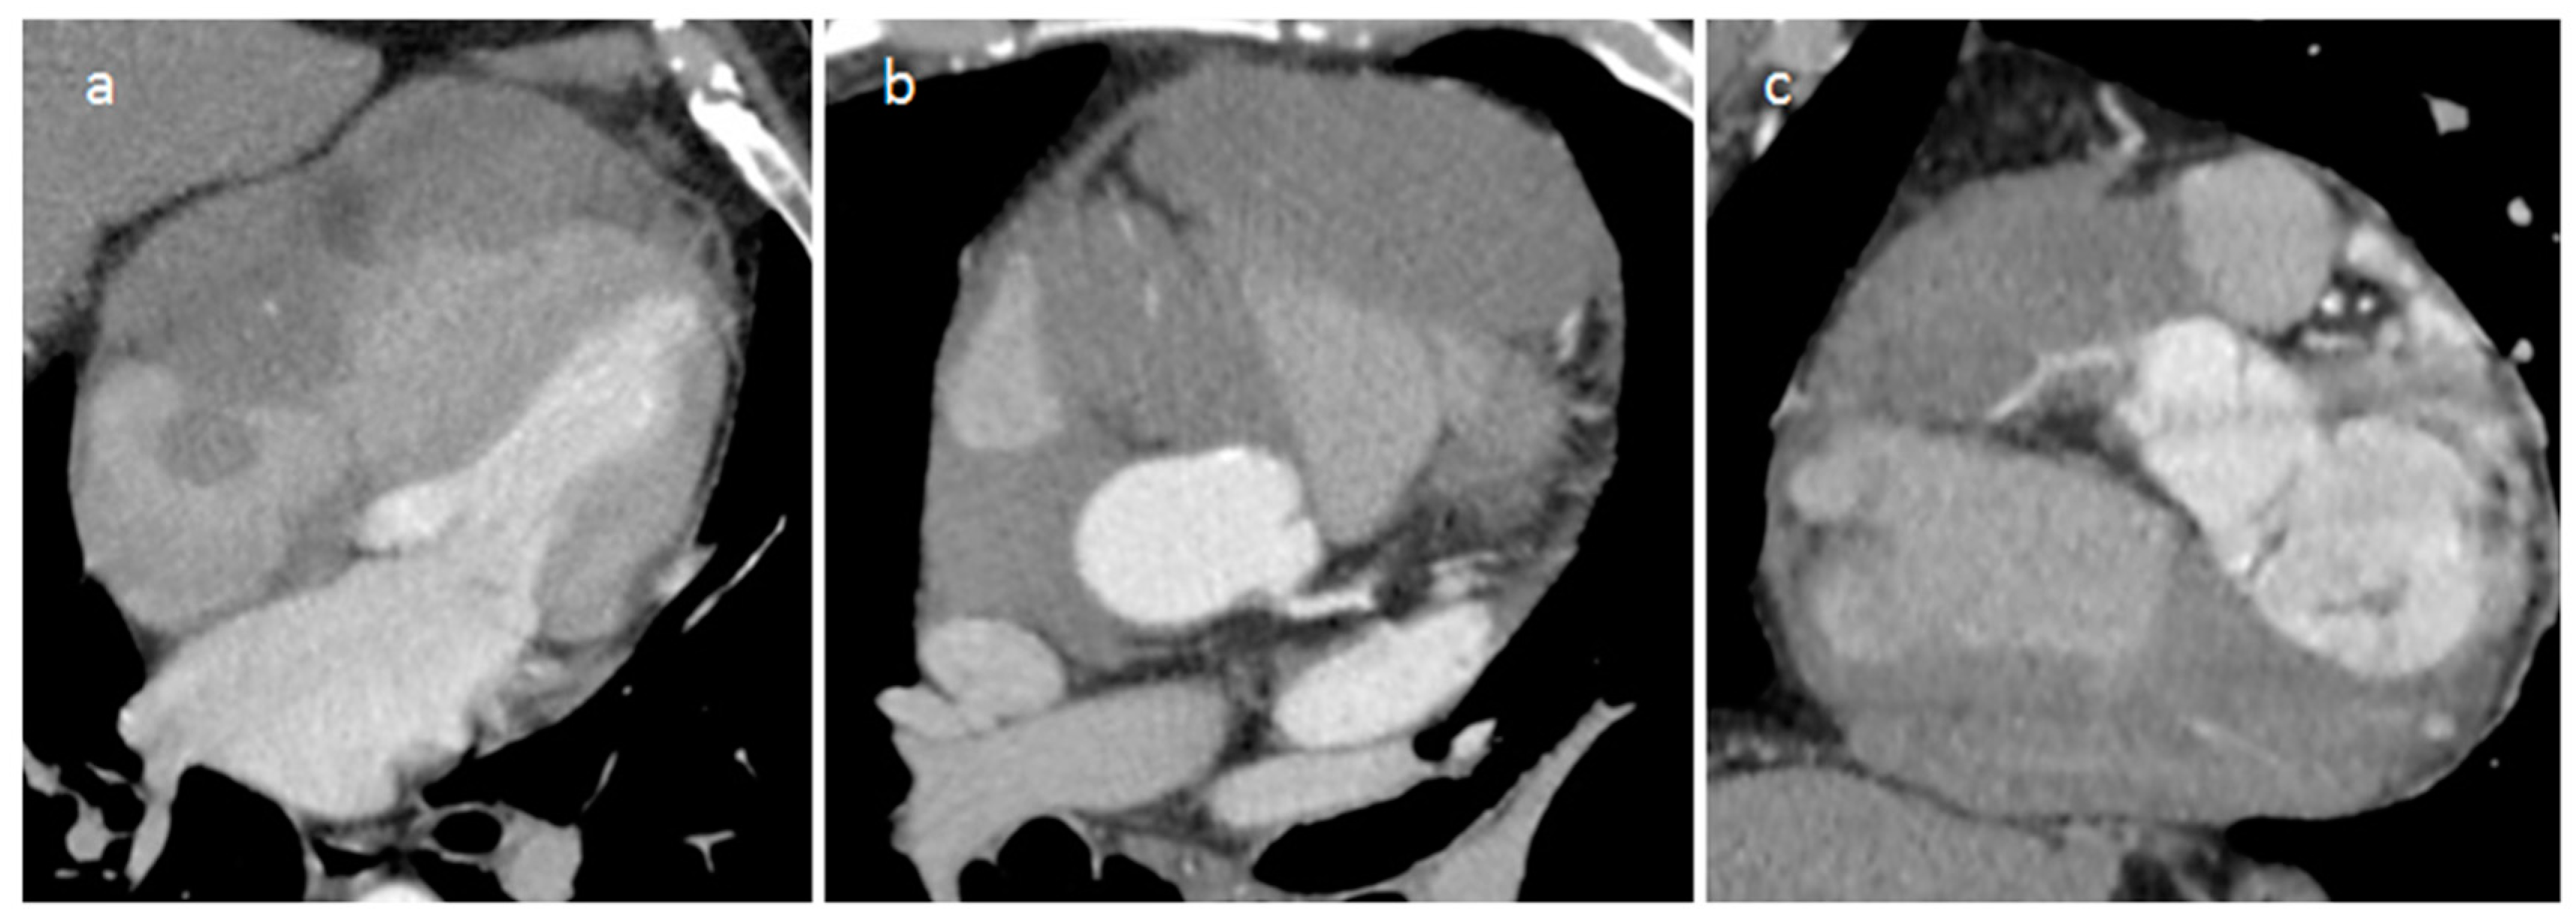

4.1. Myxoma

| Myxoma | Adulthood. Carney complex. | LA | Usually, asymptomatic. Rarely, intracardiac obstruction, embolic events and constitutional symptoms | Mobile mass arising from the IAS | Globular or spherical, with a friable surface and heterogeneous internal echogenicity | Heterogeneous, low attenuation, may be calcified | Isointense T1w, High T2w, heterogeneous LGE |